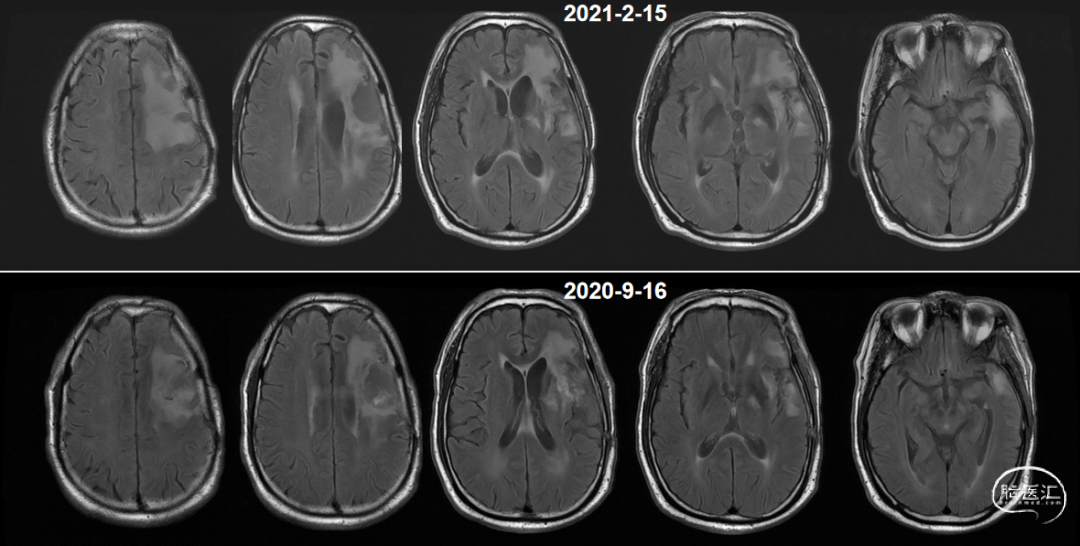

术前核磁(2020-03),左侧额岛叶肿块,信号不均匀,其内可见出血和坏死,占位效应明显,周围见水肿:图示。

术后48小时MR,可见左额不规则混杂信号影,周围水肿:图示。

肿瘤电场治疗16天,RT后1月(2020-07-22):图示。

术后5周开始实施标准的新STUPP方案的辅助治疗,即在同步放化疗后,辅助替莫唑胺化疗的同时使用了电场治疗。目前生存25月,且临床和影像学表现均提示稳定,未见复发迹象。期间,在放疗后7月时复查MRI提示异常FLAIR信号区增大,经我院MDT讨论,考虑到强化信号减轻,无明显占位效应,患者无症状体征,考虑是治疗后水肿,非进展,故继续按原方案治疗。放疗后17月复查MRI出现术区边缘局部强化范围稍增大,但PWI示强化区局部呈低灌注且未见弥散受限表现,MDT讨论考虑为假性进展,继续原方案治疗。后续复查MRI强化范围减轻,证实了MDT的判断证实疾病稳定。患者生存时间已达25个月。全程安全顺利,仅出现一过性轻度皮肤反应。

入院前头MRI(2020-3):左侧额岛叶肿块,信号不均匀,其内可见出血和坏死,占位效应明显,周围见水肿。考虑左额岛叶肿瘤(高级别脑胶质瘤可能性大)。于2020年4月行左额岛叶占位性病变切除术。术中见肿瘤组织位于左侧额中回及额下回后部,大小约4m×5cm×5cm,呈烂鱼肉样,色灰红,质软,部分坏死,血运中等,边界不清,侵犯左侧岛叶向下挤压颞叶。显微镜下沿肿瘤周边胶质增生带完整切除肿瘤。术后48小时内复查头MRI平扫、加强,影像显示术腔边缘不规则线样强化,靠近放射冠及侧脑室壁强化明显,可疑少许残存。

辅助TMZ治疗过程中每2-3月复查MRI。治疗中曾出现水肿范围增大,尽管有部分区域弥散受限和MRS异常及血流量增加,但是临床症状未加重,仍继续原方案治疗,后续监测PWI显示病变区灌注减低。提示持续肿瘤电场治疗可以使病变长期稳定。此患者每天佩戴肿瘤电场治疗时间接近22小时,中间出现头皮发红和小水泡,经局部外用皮质类固醇和外用抗生素,暂停2天治疗恢复。至今随访25月稳定。说明肿瘤电场治疗联合TMZ治疗较单TMZ治疗明显延长胶质母细胞瘤患者PFS及OS,临床应积极推广使用。